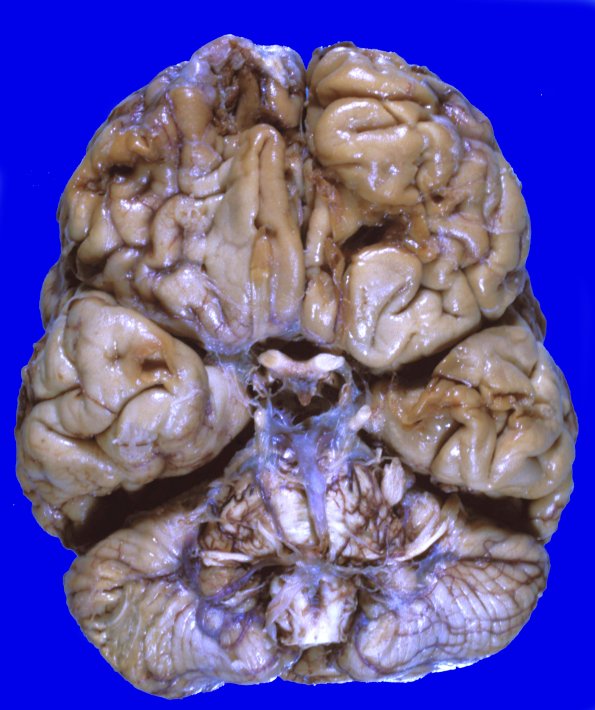

Washington University Experience | TRAUMA & FORENSIC | Contusions | 9A1 Contusion, remote (No ID) 1

Case 9 No History (No ID) An old case of the late Dr Richard Torack. ----

9A1,2 The lesions in the orbital portion of the ventral frontal lobe have been section in CT manner showing the extent of white manner involvement. Also notice the relative sparing of subcortical “U-fibers” (arrow, 9A2)